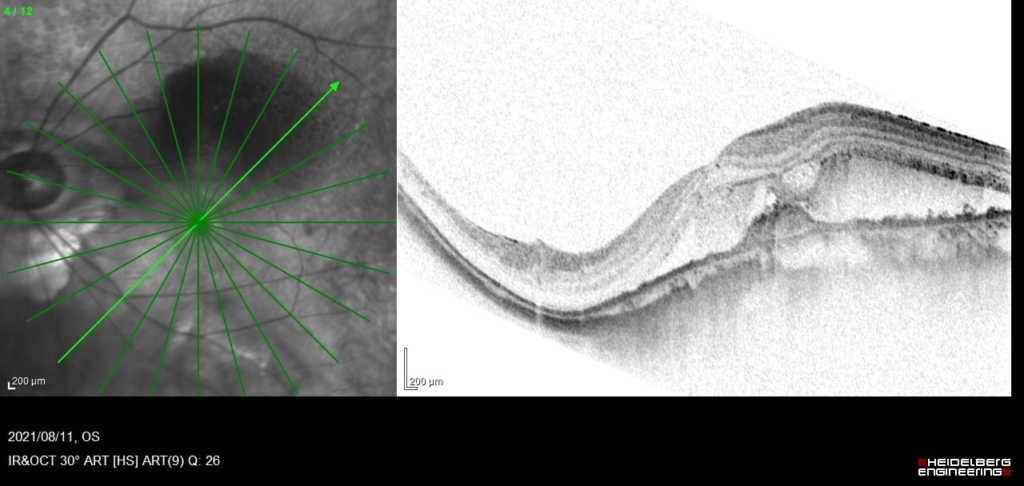

術後20日